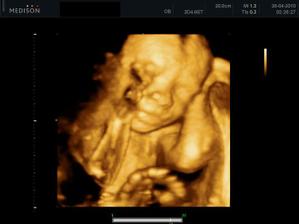

01.03. - (16+4) UTZ, dopadl dobře, měřit už nás prý paní doktorka nebude, odteď nás bude vážit.

11.05. - (26+5) dnes jedeme na video

video se povedlo, máme asi 6 cca 5 - 10ti vteřinových videíí.Bylo to super. Karolínka se zase mlela jako drak. Je taková živoučká 😀